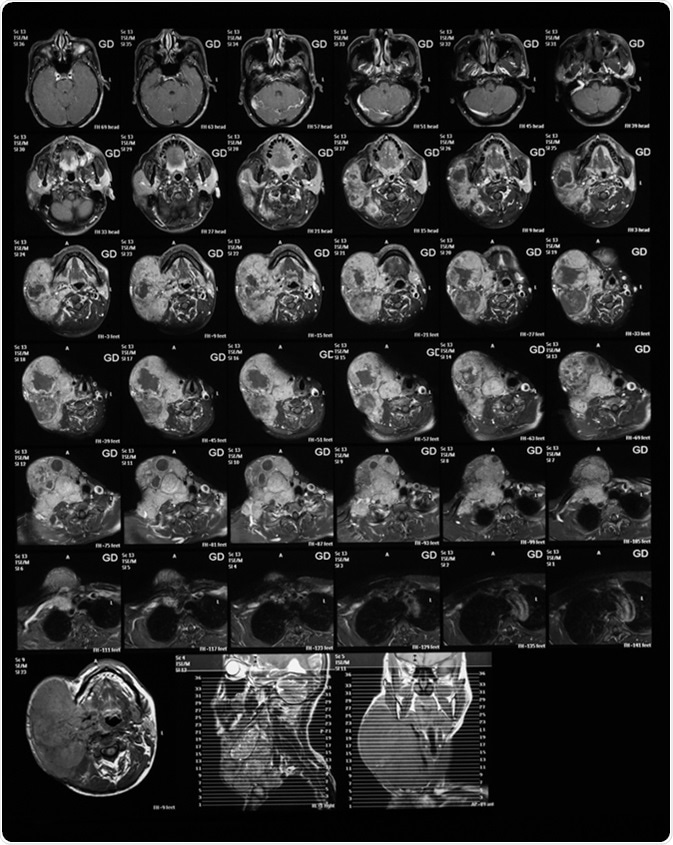

Magnetic resonance imaging of the neck with Gadolinium (GD) contrast agents, case of large right neck mass, mocoepidermoid carcinoma. Image Credit: Suttha Burawonk / Shutterstock